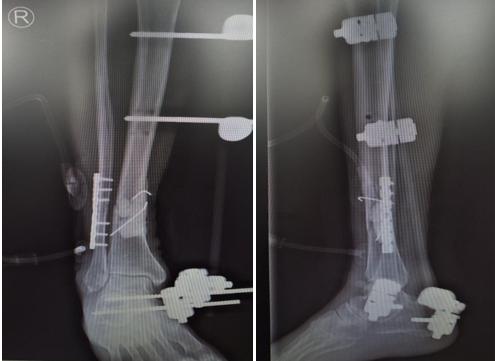

患者吴某,男性,74岁,因外伤致右胫腓骨开放粉碎骨折,右胫骨部分骨缺损7周入住市中心医院骨二科。入院诊断:右胫骨骨折骨水泥占位术后;右胫骨骨折外固定架固定术后;右腓骨骨折术后。急诊行胫骨开放骨折清创复位克氏针内固定+骨水泥占位+外固定架固定、腓骨骨折切开复位内固定、创面负压吸引术,术后定期伤口换药,预防感染等治疗。近日,在腰硬联合麻醉下行右胫骨骨水泥取除、骨折切开复位内固定、髂骨取骨植骨术,术中取部分软组织行冰冻病理切片,以高倍视野下中性粒细胞计数少于5个为标准排除感染,骨缺损处植入自体松质骨及人工骨混合物,缝合诱导膜;胫前部分切开置入内固定,术后患者伤口愈合良好。

I 期骨缺损处在体内通过骨水泥占位

II 期采用自体松质骨及同种异体骨移植+内固定术